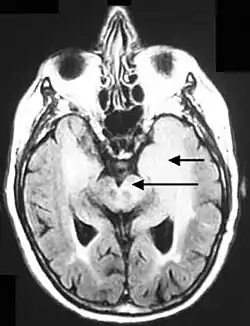

Axial fluid-attenuated inversion recovery MRI image demonstrating tumor-related infiltration involving both temporal lobes (Short arrow), and the substantia nigra (Long arrow).